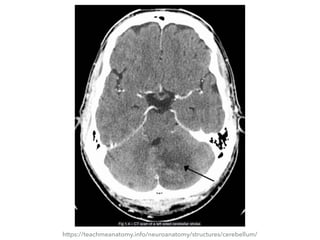

Fig 1.4 – CT scan of a left sided cerebellar stroke.

CEREBELLUM CLINICAL RELEVANCE: CEREBELLARDYSFUNCTION ▸ Dysfunction of the cerebellum can produce a wide range of symptoms and signs ▸ The etiology is varied; causes include stroke, physical trauma, tumours and chronic alcohol excess

CEREBELLUM CLINICAL RELEVANCE: CEREBELLARDYSFUNCTION ▸ The clinical picture is dependent on the functional area of the cerebellum that is affected ▸ Damage to the cerebrocerebellum and spinocerebellum presents with problems in carrying out skilled and planned movements  and in motor learning ▸ A wide variety of manifestations are possible

CEREBELLUM CLINICAL RELEVANCE: CEREBELLARDYSFUNCTION ▸ These can be remembered using the acronym ‘DANISH‘: ▸ Dysdiadochokinesia (difficulty in carrying out rapid, alternating movements) ▸ Ataxia ▸ Nystagmus (coarse) ▸ Intention tremor ▸ Scanning speech ▸ Hypotonia ▸ Damage to the vestibulocerebellum can manifest with loss of balance, abnormal gait with a wide stance